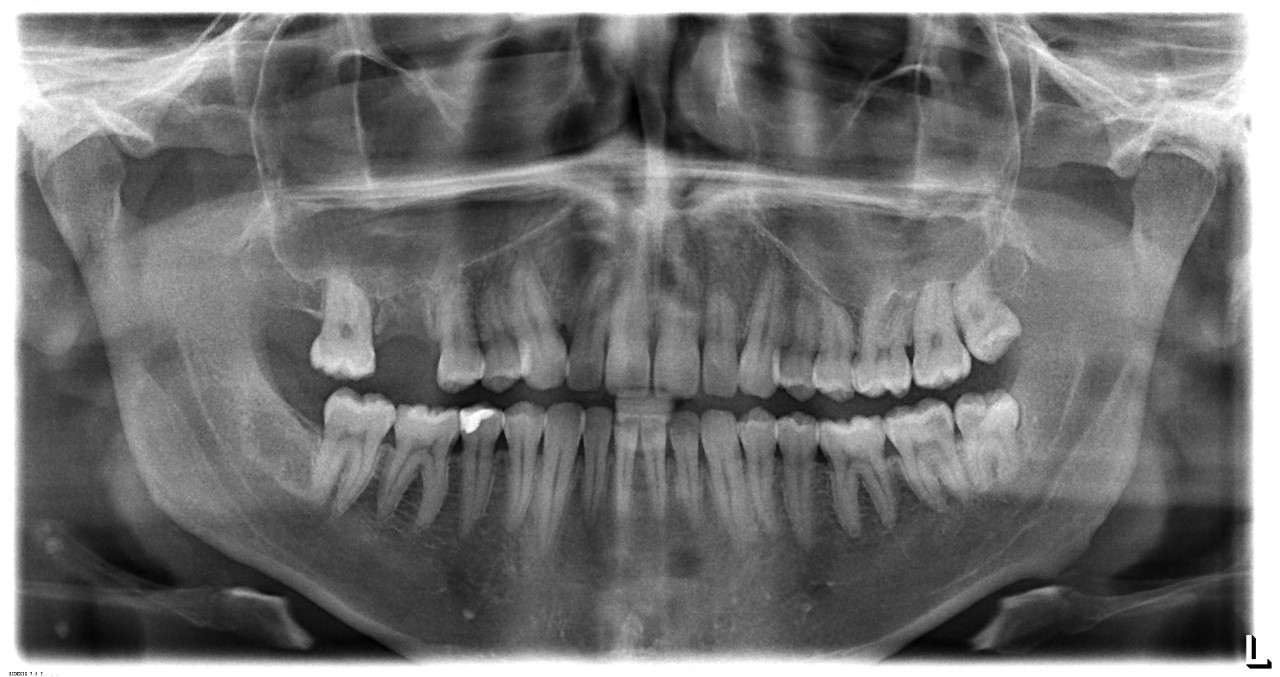

Foto heb ik nu toegevoegd, hopelijk heeft iemand wel ideeën?

We zijn dus nu weer wat verder en de pijn is weggetrokken (net zoals alle andere keren) Echter is de gevoeligheid van de plek nog steeds aanwezig, ook zitten er miniscule bultjes bij de getrokken kies. Als ik erop druk voelt het weer zoals paar weken geleden. Mijn vertrouwen is ontzettend erg beschadigd, hoe kan de kaakchirurg zeggen dat er niks te zien is ? U ziet een achtergebleven wortel ?

Zit er op dit plek dan nog een wortelrest ? en waarom in hemelsnaam ziet de kaakchirurg en tandarts niets ? prutsers ?